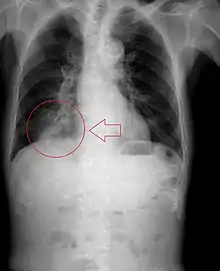

The location of abscesses caused by aspiration depends on the position one is in. If one is sitting or standing up, the aspirate ends up in the posterior basal segment of the right lower lobe. If one is on one's back, it goes to the superior segment of the right lower lobe. If one is lying on the right side, it goes to the posterior segment of the right upper lobe, or the posterior basal segment of the right upper lobe. If one is lying on the left, it goes to the lingula.